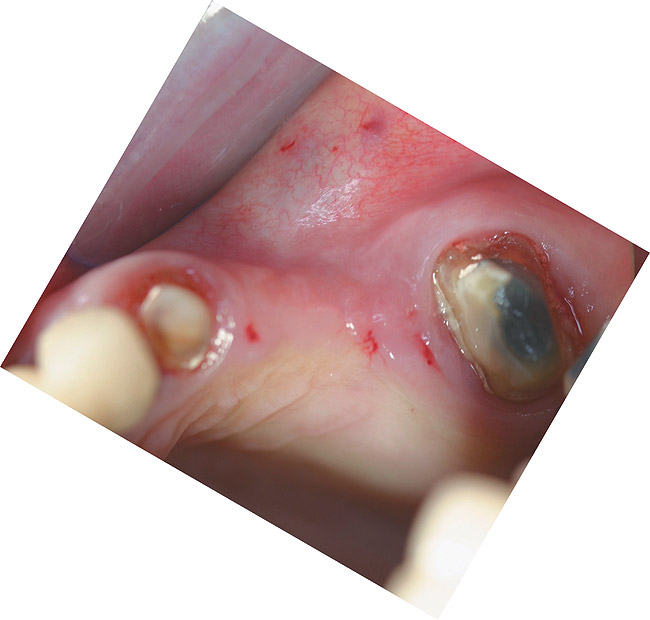

A 45-year-old man presented in the wake of a fall from a four-story scaffolding structure. His right lateral and left central incisors had been evulsed at the time of the accident, while his right central and left lateral incisors had intruded apically beyond the alveolar housing and fractured at the cementoenamel junction.

A full mucoperiosteal flap was reflected (Figure 1), and the residual roots of the two damaged teeth were extracted atraumatically, preserving the residual alveolar housing (Figure 2). Although thin, the facial plate was maintained to act as a supportive structure for the grafting material and membrane.

Figure 1  Full-thickness flap reflection exposed the left lateral incisor, which was fractured and intruded apically beyond the alveolar housing.

Figure 1

Figure 2  Occlusal view of the extracted residual roots.

Figure 2